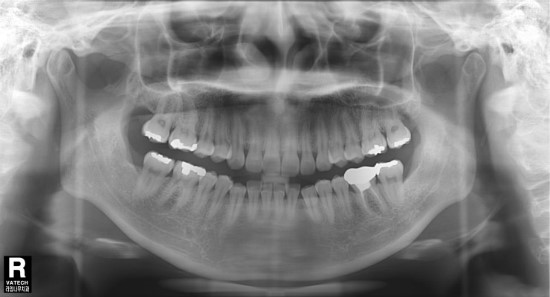

먼저 엑스레이 사진입니다,랫니가 틀어져 있는 것이 보이시죠?

아